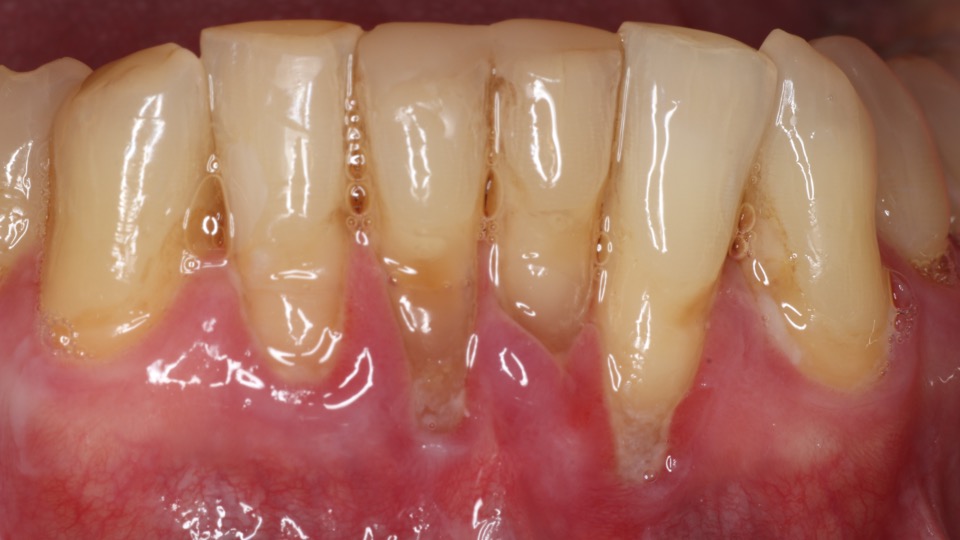

This patient is lacking all keratinized tissue. They only have thin alveolar mucosa surrounding their teeth which is leading to both recession and bone loss.

Take a closer look at the difference between the two areas in this patient's mouth. The teeth surrounded by thick, firmly attached protective tissue show no plaque buildup, no inflammation, and stable, healthy gum levels. In contrast, the sites that lack this protective tissue are visibly inflamed and collecting bacteria along the gumline, which is driving progressive recession. Without intervention to rebuild that protective barrier through grafting, the affected teeth would continue to lose gum tissue and bone support over time, ultimately putting them at risk of being lost entirely.